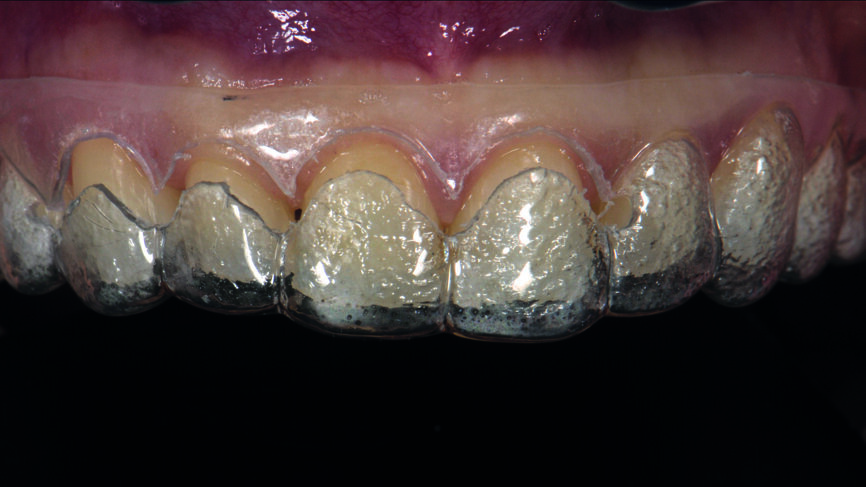

Une patiente âgée de 35 ans s‘est présentée au cabinet dentaire avec le souhait profond d‘un changement de l‘esthétique de la région antérieure (Fig. 1). Une maquette en cire diagnostique a été réalisée puis un mock-up en composite, afin d‘avoir une représentation préliminaire du résultat final.

Fig. 1 : Photographie initiale des dents antérieures avant le traitement orthodontique

Le traitement orthodontique proposé visait à un alignement plus favorable des dents de façon à ne requérir qu‘une préparation minimale pour la pose des facettes et à réduire le recouvrement incisif. Une année après le traitement, la patiente est revenue pour la restauration prothétique définitive (Figs. 2a et b).